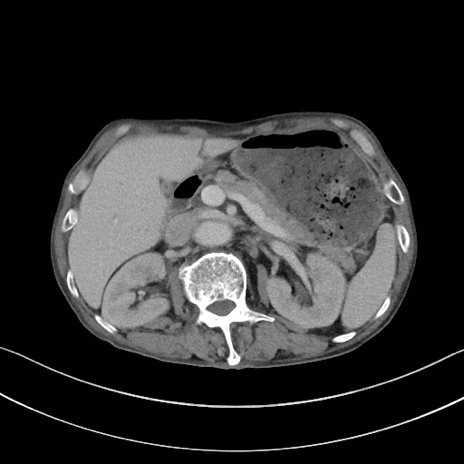

症例3(横断像)

【症例】 70歳代男性

【主訴】右鼠径部腫瘤、疼痛

【現病歴】本日朝より上記主訴あり、受診。

【既往歴】膀胱癌にて膀胱全摘、両側尿管皮膚瘻

【データ】WBC 5600、CRP 0.56